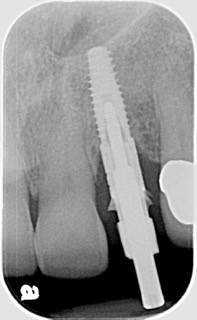

Both Caroline’s and Karen’s lateral incisors were removed, and immediate implants were placed. Although the implant surgeons were different, they were both long-time members of my interdisciplinary team and had significant implant placement experience. Both implants were torqued to 50 Ncm at the time of placement. Provisionals were then placed by me that same day.

Following four months of healing, Karen was appointed in my office for the final restoration of the implant. The provisional was removed, without anesthesia, and the implant impression post was secured to the newly healed implant. The restorative process was uneventful, and a ceramic restoration and gold post were placed.

This intimacy is referred to as the bone-to-implant contact. It is a function of both the implant length and diameter (BIC). This intimate contact provides the primary stability of the implant. Acceptable stability is verified through the torque testing at the time of placement. 50 Ncm or greater torque is considered acceptable for immediate implant loading.

Regardless of the BIC, micro and mini “gaps” exist at the bone/implant interface. These “gaps” fill with blood and ultimately form clots. Ideally, bone will replace these clots through resorption/replacement. The oxidized layer of the titanium implant creates a cellular response that promotes adhesion and cellular proliferation. This is the “structural” component of healing implants. The “static” aspect of primary stability is essential to allow adequate healing to occur before “loading” of the implant.

Lastly, implant diameter and length are significant considerations in implant stability. The longer the implant, the greater the surgeon’s ability to engage bone and achieve primary stability, especially in an immediate extraction — immediate placement scenario. Wider implants provide greater BIC for healing, but implant stability and the emergence profiles of the abutment are limitations for a “wider is better” concept. Ultimately, force management is the key to successful implant integration and longevity!